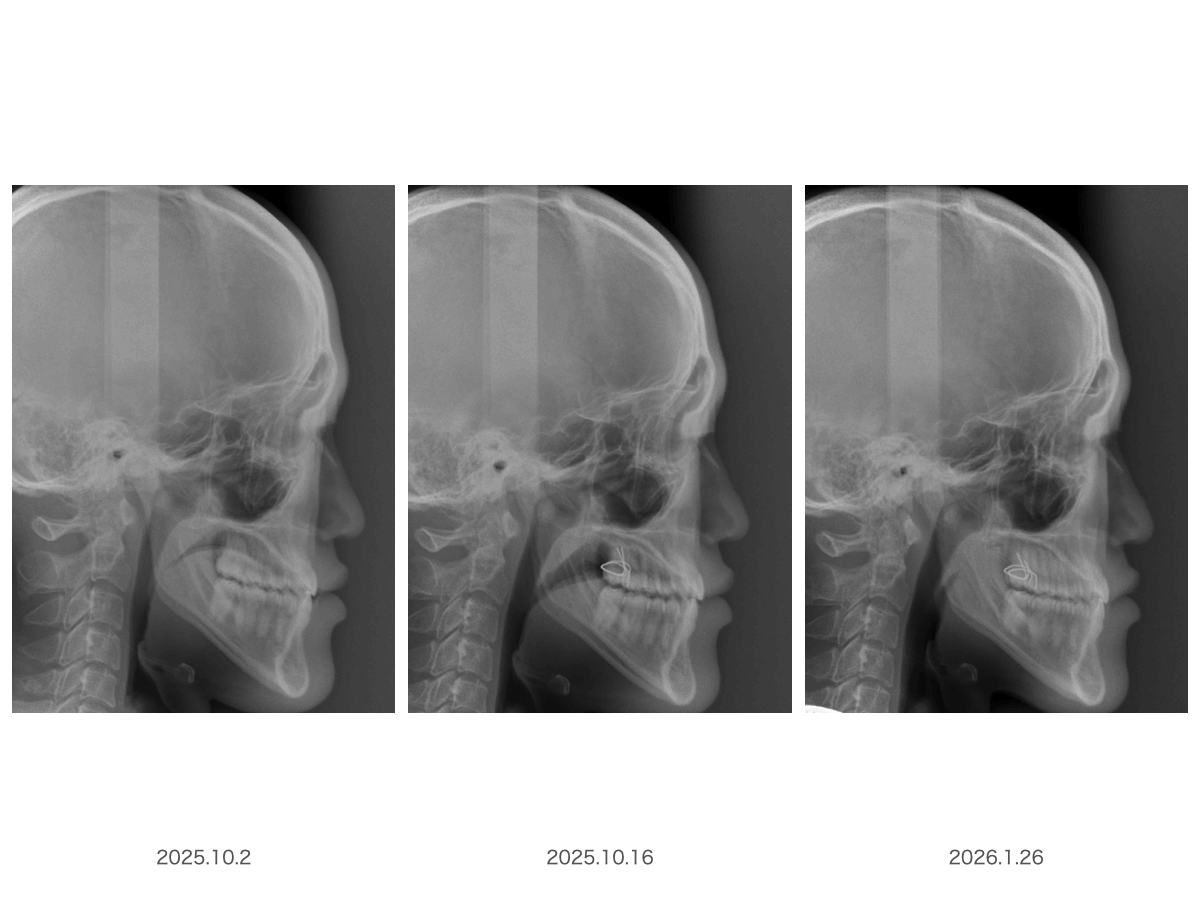

ここに3枚のレントゲンがありますが、もちろん同一人物であり、昨年10月2日からの変化になります

よく見比べてみて何が違うのか探してみてください・・・・

例えば画像を拡大してみたり。。。。

咽頭部を拡大してみたらいかがでしょう?